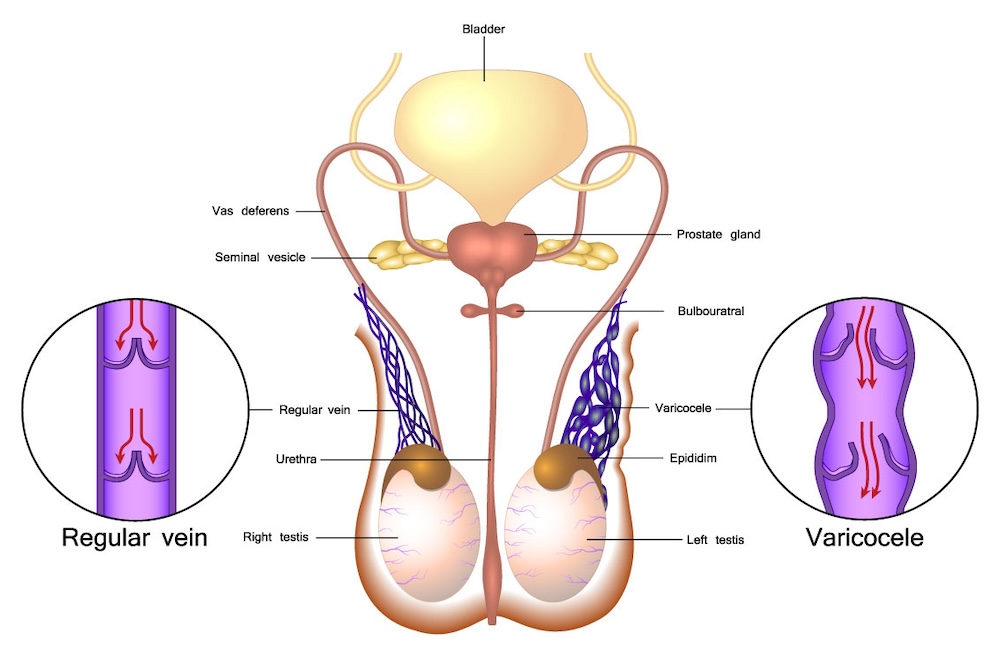

Varicocele is a medical term referring to the enlargement of veins within the scrotum, the pouch of skin that houses the testicles. These veins, similar to varicose veins that occur in the legs, become dilated and engorged due to the pooling of blood. This condition predominantly affects the left side of the scrotum.

Enlarged Scrotal Veins: Swollen veins in the scrotum impacting blood flow can cause dull pain and potential testicular atrophy. Dr. Nagesh utilizes advanced diagnostics to pinpoint the issue, crafting personalized treatment plans that often include minimally invasive procedures for effective symptom relief.

Male Infertility: Varicoceles are a common contributor to male infertility, disrupting sperm production. Dr. Nagesh adopts fertility-focused interventions, including varicocele repair procedures, to enhance reproductive outcomes for couples facing infertility challenges.

As an experienced urologist, Dr. Chinmay Nagesh employs a personalized and comprehensive approach to address varicoceles. His diagnostic precision, coupled with a range of treatment options, ensures that each patient receives tailored care based on their unique circumstances. Whether it’s managing symptoms or addressing concerns related to fertility, Dr. Nagesh’s expertise aims to provide optimal outcomes and improve the overall quality of life for individuals dealing with varicocele.